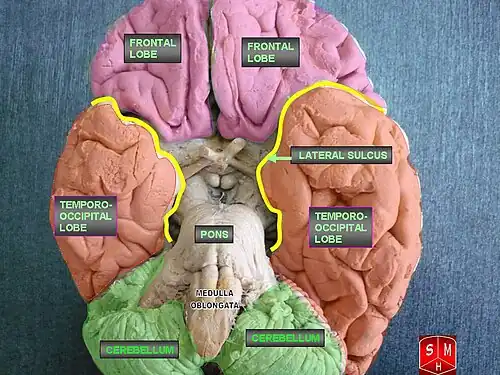

LENAS is seen with damage to the white matter and axons within the brain. The external human LENAS brain shows findings in several major structures. There is mild atrophy of the frontoparietal regions of the brain and a mild reduction of the thalamus and rostral (front) part of the caudate nucleus (which is located in an area of the brain called the basal ganglia).[5] Abnormalities in the frontal, frontoparietal, and temporal lobes are most severe and predominant with LENAS and asymmetry of the cerebral hemispheres has sometimes been found.[5] LENAS also may show moderately enlarged lateral ventricles and atrophy in corticospinal tracts as well as in the pons.[5]

The area where it is seen to be the most pronounced abnormalities appear in the white matter below the pre- and postcentral gyri that extend through the posterior limb of the internal capsule into pyramidal tracts of the brain stem.[5]

- The corpus callosum is variably affected.

- Reactive astrocytes and macrophages are present, but no inflammation appears.

- The cerebral cortex and basal ganglia are normal and contain no or only few spheroids.

- Within the cerebellum, there is a marked loss of Purkinje cells seen but cerebral white matter is normal.

Normally, the frontal lobe in our brain are important for our higher level executive functions. Predominance of white matter damage in this lobe has been found to be consistent with both the psychiatric and behavioral signs and symptoms pertaining to LENAS.[10] The underlying symptoms seen of frontotemporal dementia seen commonly in LENAS is associated with the temporal lobe damage.[10] There is a large disconnect in the brain between the lobes that reflect the neuropsychiatric symptoms that are common with the disease.[10]

Ataxia, which is related to our daily voluntary movements of muscles, are often present even in patients without cerebellar involvement which could reflect either minimal damage to the cerebellum or diffuse cerebral white matter lesions.[10]